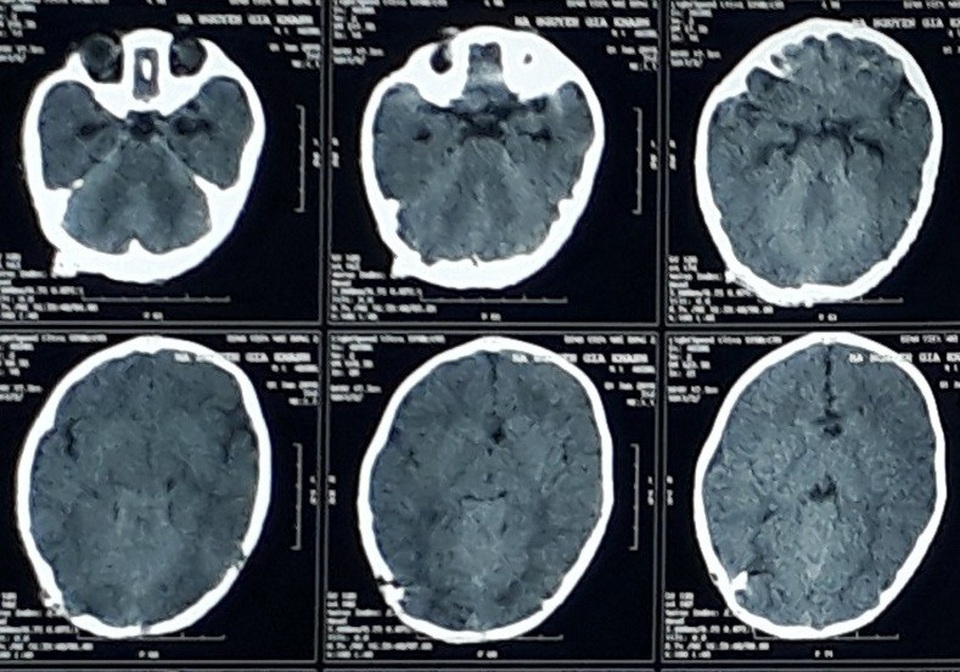

Sau các kết quả thăm khám, chẩn đoán hình ảnh, bác sĩ khoa Ngoại Thần kinh, Bệnh viện Nhi Đồng 2 xác định bệnh nhi bị não úng thủy do dính khớp sọ. “Lúc đó chúng tôi rất sợ, sốc. Vợ tôi khóc suốt vì không biết con mình sẽ như thế nào với phần đời còn lại khi đầu ngày càng phình to” - anh T.A. (38 tuổi, bố bệnh nhi) chia sẻ.

Khi được 3 tháng tuổi, cháu được các bác sĩ phẫu thuật dẫn lưu não thất - ổ bụng. Lên 9 tháng tuổi, các bác sĩ tiếp tục thực hiện cuộc mổ mở rộng sọ chẩm cho bệnh nhi. Ngày 26/7, khi được 13 tháng tuổi, các bác sĩ vừa thực hiện thành công cuộc phẫu thuật tạo hình mở rộng trán, ổ mắt cho bệnh nhi. Hiện, bé đang trong giai đoạn hậu phẫu, sức khỏe ổn định.

Một trường hợp khác là bé T.P. (17 tháng tuổi) cũng vừa được bệnh viện can thiệp phẫu thuật mang lại kết quả khả quan. Sau chào đời bác sĩ chẩn đoán Bé T.P. bị dính khớp trán, não úng thủy, thoát vị não chẩm. Bệnh nhi được phẫu thuật đặt dẫn lưu não thất - ổ bụng do não úng thủy sau sinh 2 tuần và mổ cắt khối thoát vị não chẩm lúc 6 tháng tuổi.

Mới đây, ê kíp phẫu thuật tiếp tục thực hiện cuộc mổ tạo hình trán - ổ mắt để chỉnh hình dị tật dính khớp sọ trán cho bệnh nhi. Sau 2 tuần phẫu thuật tạo hình, bệnh nhi hồi phục tốt, nhận thức và sinh hoạt bình thường.